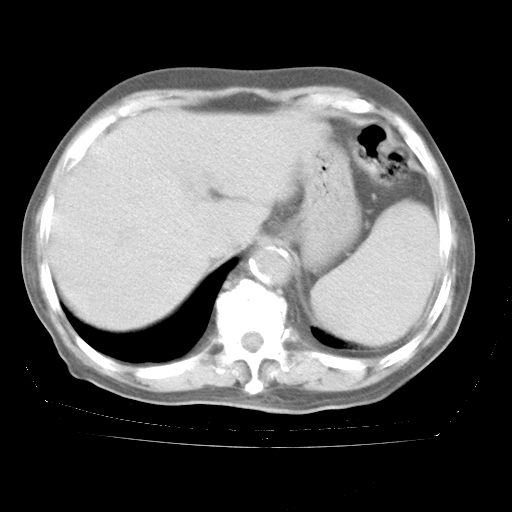

个人阅读4.14日肺部CT平扫:纵隔窗无异常,但肺窗示:双下肺内、后基底段有片絮状侵润影,部位以后基底段为著,以间质改变为主,呈急性肺泡炎征像,和首次住院影像学有相似之处。仅是个人读片,明日请相关专家再读片哈。其它建议同上。

1、108#的是4月14日的胸部CT(发此贴时还没看着28日的CT)。14日的胸部CT其实已经出现改变(如108#所述),个人认为28日的胸部CT除纵膈窗疑似有双侧胸膜增厚或少量胸积液(可行胸部B超明确)外,与4月14日对照病变有所加重;2、已经给予“异烟肼、利福平、乙胺丁醇”抗痨治疗?如果是,甲强龙80mg可缓慢减量;如果环磷酰胺已停用,暂不使用;3、中性粒细胞92%,明显升高,目前体温情况?注意合并细菌感染可能,使用左氧氟沙星情况下,是否联用B-内酰胺类抗菌药物?另外是查免疫全套非风湿全套。

今请临免主任会诊后认为:4月14日胸部CT已有双下肺间质性改变。患者病情复发多系激素减量过快不正规所致。目前甲强龙80mg/日,一周后酌情开始减量,不易过快。环磷酰胺若已停用,暂不使用。他同意目前抗菌药物使用,但应考虑是否加用B-内酰胺类抗菌药物(中性细胞明显增高);2、结核复发目前依据不足;3、若免疫全套各项指标正常,考虑多系特发性肺间质炎可能大。4、加强支持,并注意保护胃黏膜。